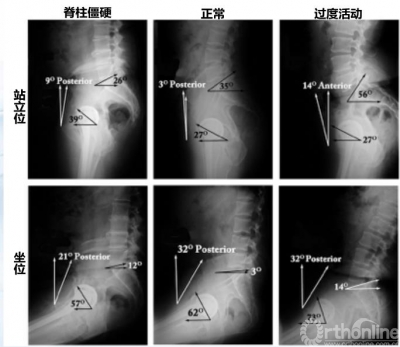

图4 站立位到坐位髋臼角度的变化

图5 1例髋关节脱位患者髋臼角度的变化

坐位时髋臼前倾角变大,可以影响稳定性、增加边缘磨损、甚至脱位。对于骨盆活动度大患者,髋臼外展角>50°, 前倾角>25°,脱位的危险也明显增大。既往研究显示,从站立位到坐位,髋臼前倾增加7.1°,骨盆后倾增加14.5°;在矢状面上,坐位时骨盆后倾增加30°,髋臼前倾增加30.2°。